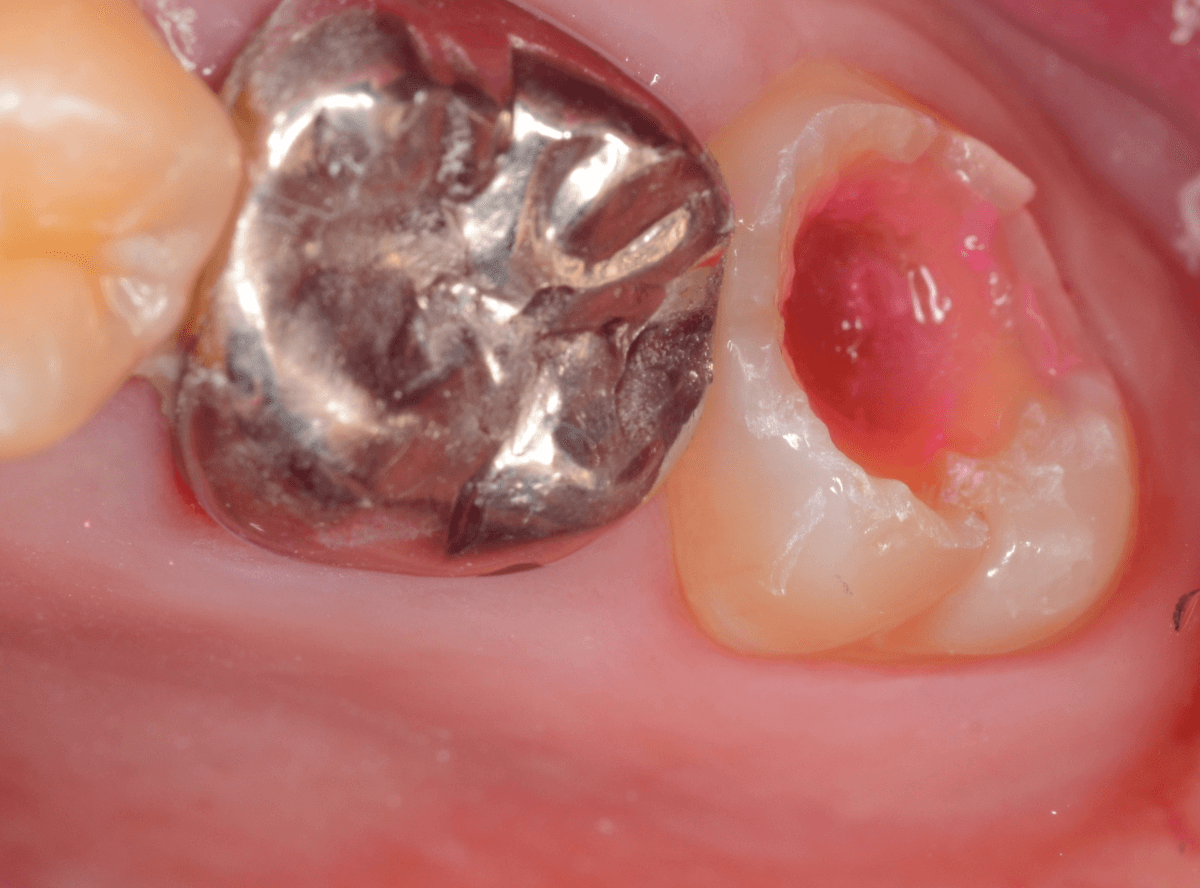

「下の一番奥の歯が痛い」という訴えで来院された患者さんの例です。

一見では、特に問題ないように見えます。

治療を開始します。

歯の奥の部分を少し削ると、虫歯が出てきました。

慎重に虫歯を除去します。

歯肉ラインの下まで虫歯が進行しているため、虫歯の上に歯肉が広がっており、虫歯の見分けがつきづらい状況になっています。

虫歯を取り残さないように、余分な歯肉を除去します。

電気メスで、虫歯周囲の歯肉を除去後、全ての虫歯を除去しました。

虫歯は深かったですが、なんとか神経寸前のところで食い止められました。

神経を保護するお薬をつめて、セメントで蓋をしてしばらく経過観察します。

経過観察後、痛みがない事が確認できれば、つめものを作製します。